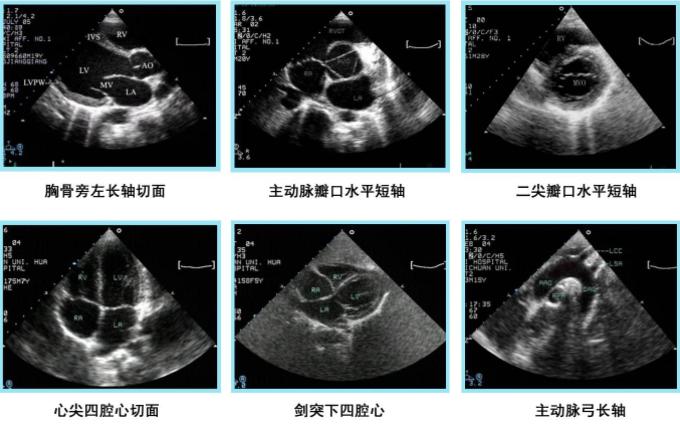

2、二维切面成像

B型超声成像系统:又称超声断层法,或灰阶超声成像,目前应用Z广。光点显示,亮度随回声信号变化,深度扫描为垂直方向,位移扫描为水平方向,构成切面显示图。

超声成像系统经历了黑白、灰阶、彩阶和彩色;该显像空间技术有1D、2D、3D到多普勒;时间由慢扫描发展为快扫描;时态由3D静态发展为3D动态;按物理参数,分幅度法和频移法;在聚焦技术上由模拟超声发展为数字超声。